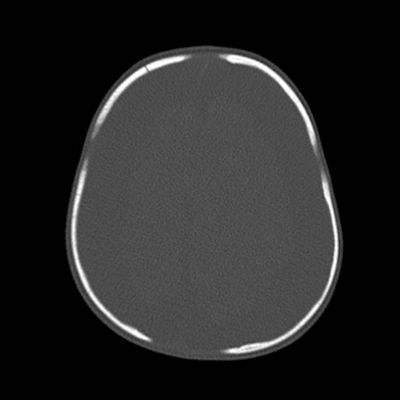

- B) Kemik pencerede frontal kemikte sağda nondeplase kırık

- C) Süturlarda ayrışma